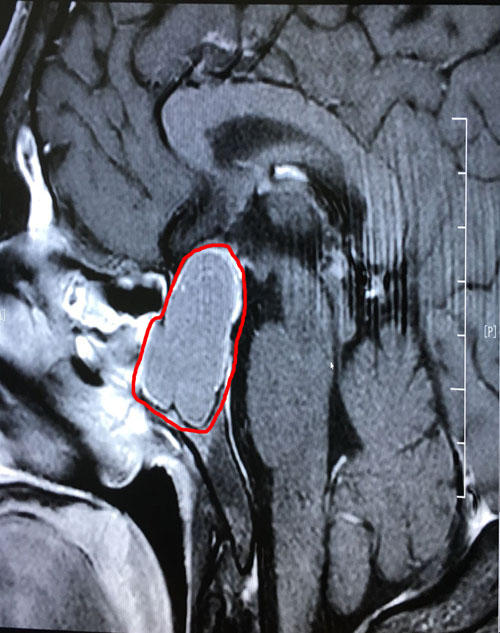

术前影像显示:垂体巨大腺瘤,突破鞍隔向上生长

到院后,李士其教授和潘仁龙主任一起,研究讨论了患者病情:由于患者颅内鞍区的肿瘤很大(约1.8*3.1公分),已严重影响到患者的垂体功能,并压迫视神经,感觉神经等功能。李士其教授表示:手术是刻不容缓的事,待患者检查结果出来,没有手术禁忌,就可以立即实施手术。

术后第二天影像:肿瘤切除干净,鞍内脑脊液填充